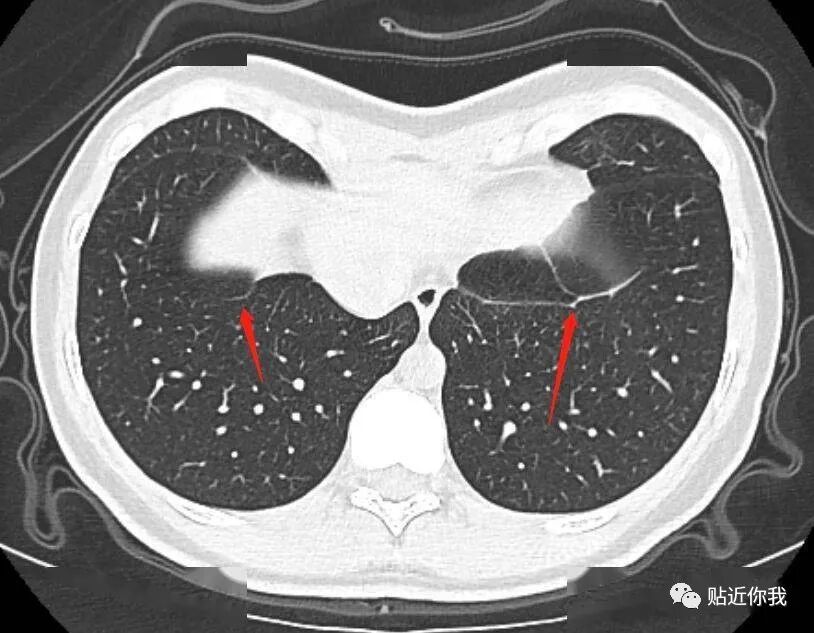

1.肺部CT发现“条索影”

过往的CT检查中,如果发现肺部出现“条索影”,而且随着时间的推移逐渐增多、增大,这可能是肺癌的信号。在这种情况下,及时进行进一步检查是至关重要的,因为早期的发现有助于更好地制定治疗方案。